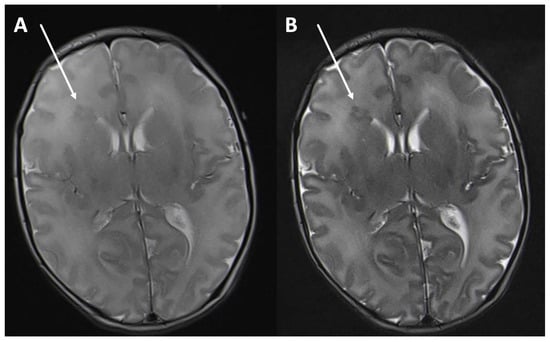

| 6–10 | 18 | −0.02 | −0.01 | −0.05 | 0.00 | 0.24 |